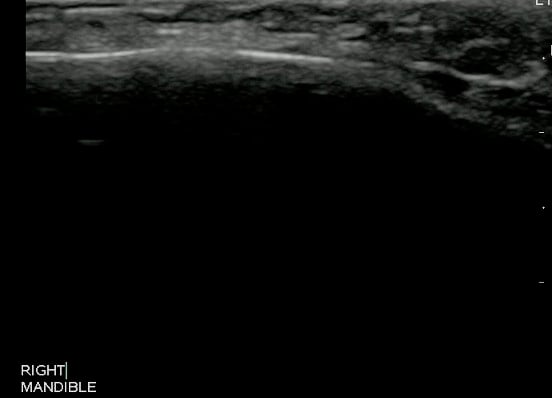

- Figure 5 and 6. Normal Mandible

- Bony structures like mandible, maxilla appear hyperechoic with a posterior hypoechoic acoustic shadow underneath.

- Fat has hyperechoic appearance on ultrasound.

- Muscles are generally visualized as hypoechoic structures but have a more heterogeneous striated appearance.

- Normal Mandible:

Video 4. Normal Mandible